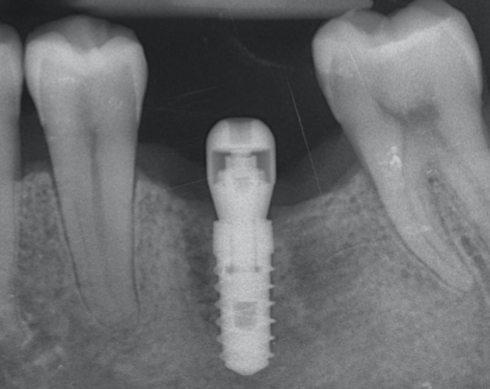

Les implants dentaires sont des racines artificielles sous forme de vis en titane. Ils sont insérés dans l’os de la mâchoire permettant de remplacer une ou plusieurs dents absentes.

La mise en place d’un implant requiert une étude pré-implantaire. Cette évaluation permet de valider le volume et la qualité osseuse disponible afin de placer l’implant dentaire dans une position idéale et esthétique. Si l’étude pré implantaire montre un manque d’os, une greffe osseuse (ROG, sinus lift) sera nécessaire.

L’implant dentaire peut être posé sur une crête osseuse cicatrisée (plus de 3 mois après l’extraction) ou le même jour que l’extraction. La prothèse définitive est confectionnée après la solidification de l’os autour de l’implant (osteointégration). Dans certaines conditions, une prothèse provisoire peut être mise en place immédiatement après la pose de l’implant.